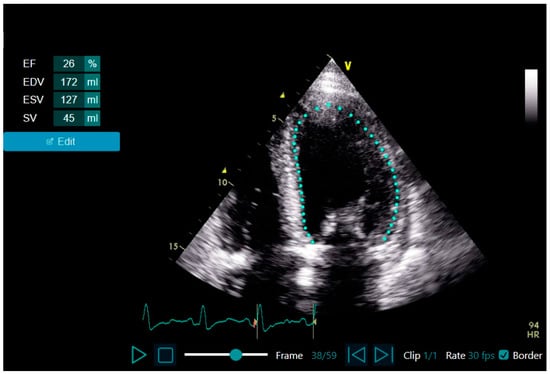

2.4. Echocardiogram Acquisition and LVEF Assessment Using LVivo EF vs. Expert Assessment